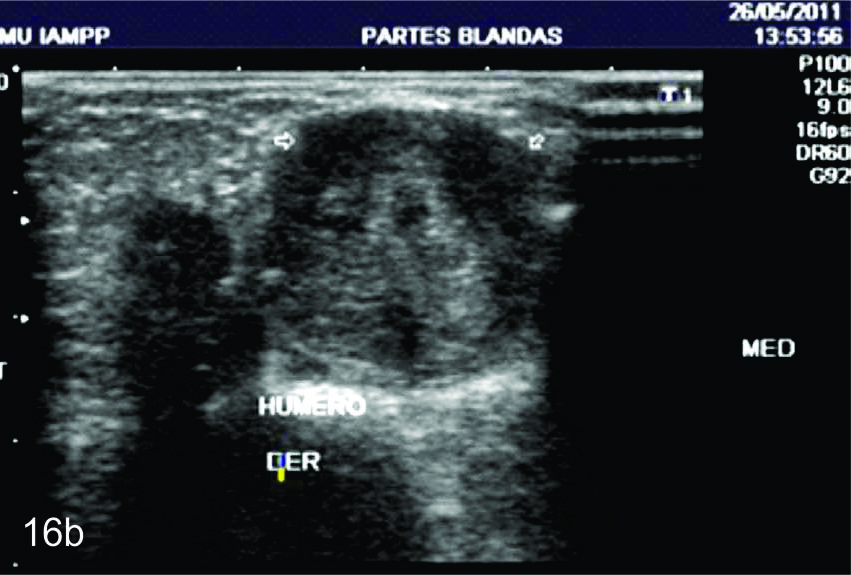

Figura 8

Nervio mediano

Serie de cortes axiales del nervio mediano desde su origen a nivel del hueco axilar hasta el sector distal del antebrazo previo a su ingreso al túnel del carpo. Se identifica el mismo señalado por flechas amarillas y con la palabra mediano. AA-arteria axilar, VA- vena axilar, AH- arteria humeral, VH- vena humeral, VB- vena basilar, AC- ateria cubital, VC- vena cubital, BA- músculo braquial anterior, PR- músculo pronador cuadrado, FS- músculo flexos superficial, FP- músculo flexor profundo, PC- músculo pronador cuadrado. A- axila, se identifica el nervio superfical a la arteria axilar, B- tercio medio del brazo en canal bicipital medial, lateral a la arteria humeral, C- codo, medial al tendón distal del bíceps braquial y a la arteria humeral luego de cruzarla, superficial al músculo braquial anterior, D-antebrazo sector cefálico, entre las dos cabezas del pronador redondo, E- tercio medio del antebrazo, entre los músculos flexor superficial y profundo F- tercio distal antebrazo, superficial al pronador cuadrado.